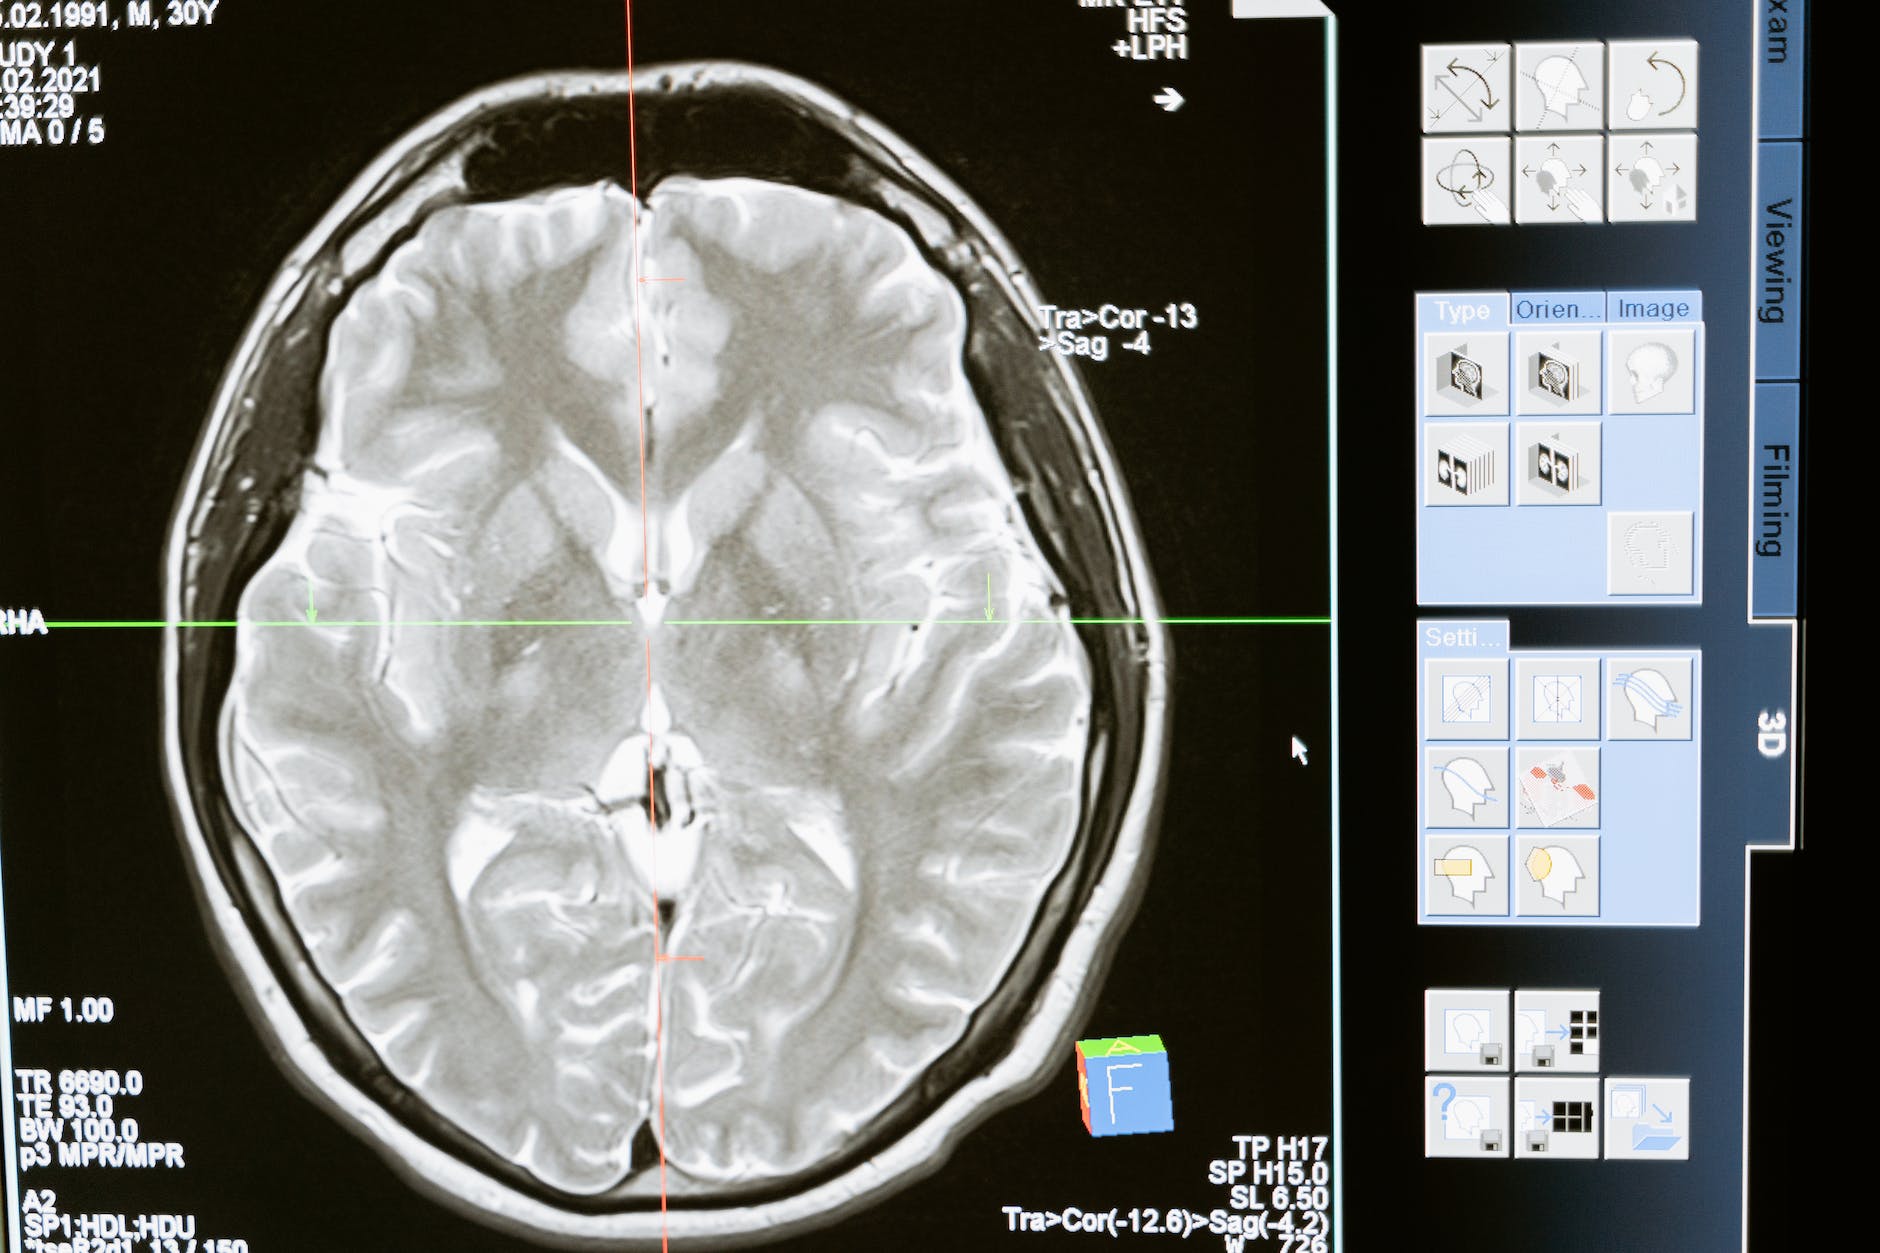

ويعد وليد صديق، مبتعث سعودي من برنامج خادم الحرمين الشريفين للابتعاث الخارجي، وقد استعان خلال بحثه للتوصل لحل لقتل سرطانات الدماع بفيروسات البرد ” HSV” المعدلة جينيا، بحيث تكون مختصة بقتل السرطانات، ويتم ذلك عبر نقلها إلى المريض بواسطة الخلايا الجذعية الخاصة به، والتي بدورها تلعب دورا حيويا في انتقال الفيروسات بشكل دقيق إلى موقع السرطان في الدماغ.

وخلال تصريحاته لـ”واس” أكد صديق أن الأدوية الحالية لعلاج سرطانات الدماغ لا تستطيع عبور الحاجز الدموي الخاص بالدماغ، الأمر الذي يجعل علاج مريض سرطان الدماغ أمرا صعبا للغاية.